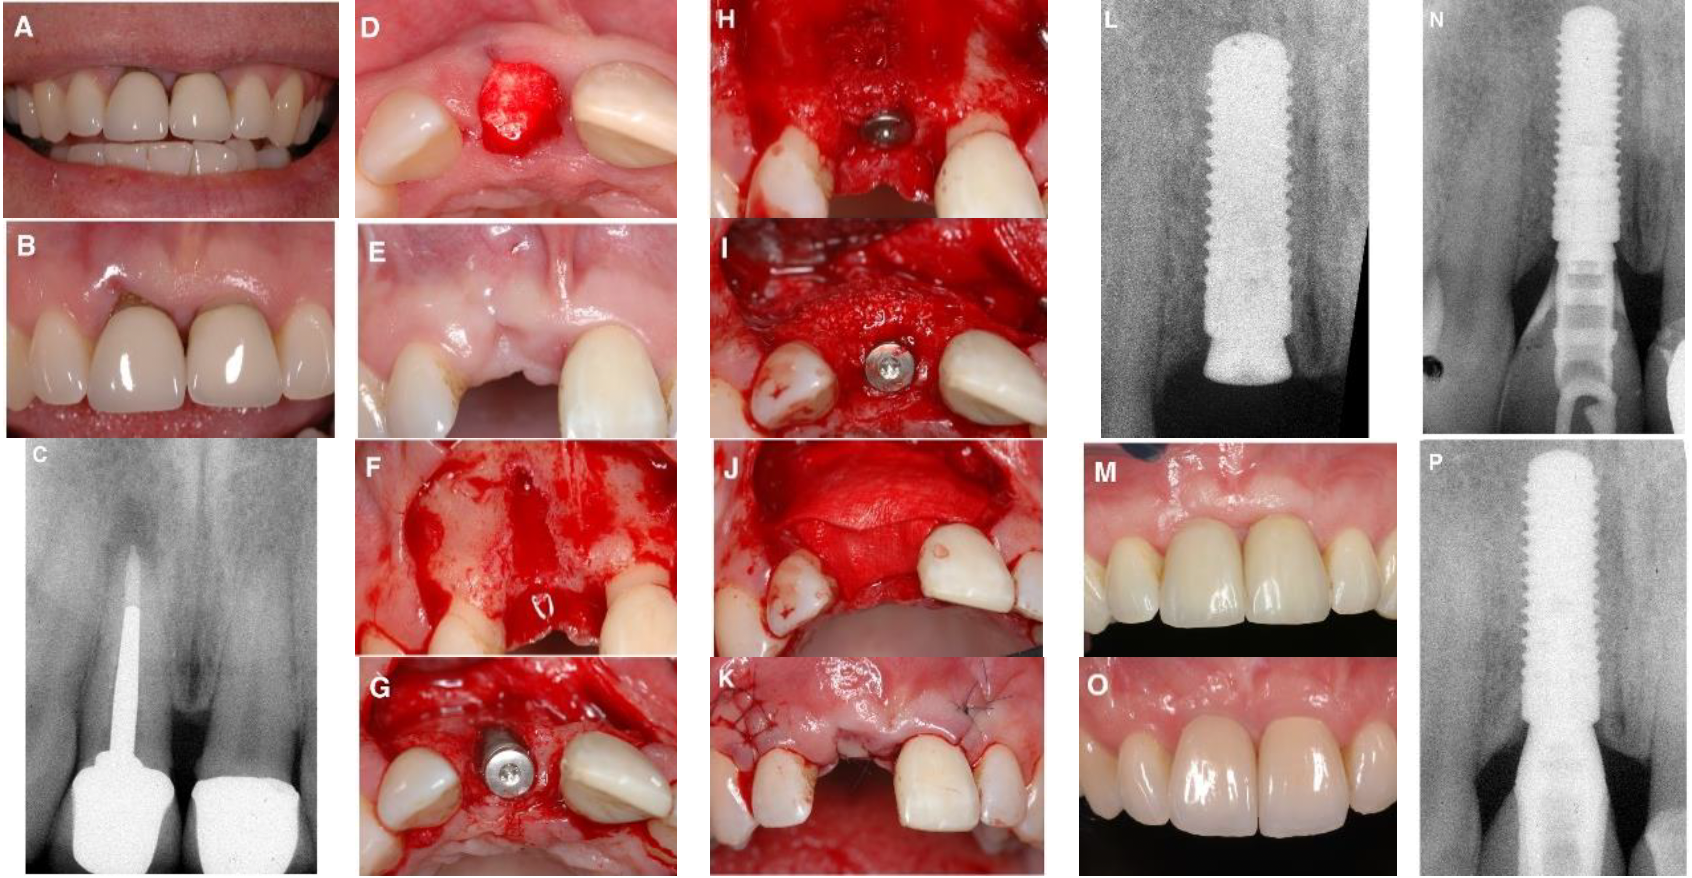

Type I

- 即拔即種

- 保留原本的骨頭

Type II

- 4-8w

- 唇側沒有骨頭

- 先讓軟組織長夠多再來GBR植牙

- 用膠原蛋白

- 軟組織總量夠多就不須做tension release